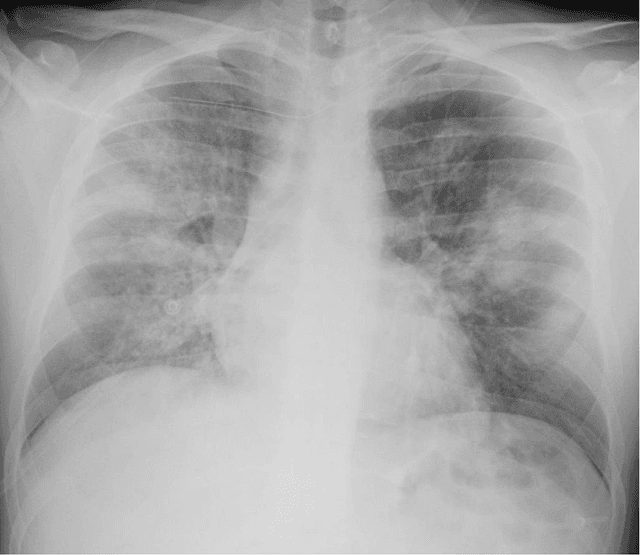

Purpose: This study aimed to develop and validate computer-aided diagnosis (CXDx) system for classification between COVID-19 pneumonia, non-COVID-19 pneumonia, and the healthy on chest X-ray (CXR) images. Materials and Methods: From two public datasets, 1248 CXR images were obtained, which included 215, 533, and 500 CXR images of COVID-19 pneumonia patients, non-COVID-19 pneumonia patients, and the healthy samples. The proposed CADx system utilized VGG16 as a pre-trained model and combination of conventional method and mixup as data augmentation methods. Other types of pre-trained models were compared with the VGG16-based model. Single type or no data augmentation methods were also evaluated. Splitting of training/validation/test sets was used when building and evaluating the CADx system. Three-category accuracy was evaluated for test set with 125 CXR images. Results: The three-category accuracy of the CAD system was 83.6% between COVID-19 pneumonia, non-COVID-19 pneumonia, and the healthy. Sensitivity for COVID-19 pneumonia was more than 90%. The combination of conventional method and mixup was more useful than single type or no data augmentation method. Conclusion: This study was able to create an accurate CADx system for the 3-category classification. Source code of our CADx system is available as open source for COVID-19 research.